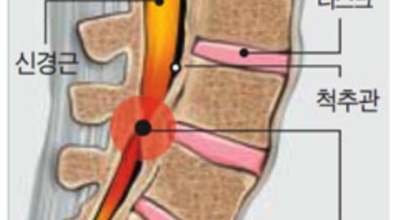

척추관 협착증이란 신경이 지나가는 통로인 척추관이 좁아진 상태를 말하며 척추관 협착증이란 용어는 주로 요추부(허리)에서 사용합니다. 척추관 협착증 환자는 정상에 비해서 척추관이 좁아져 신경이 압박받게 돼요.

정상인 사람은 척추가 완만히 휘어져 있는데 척추관 협착증인 사람은 더 일자로 펴져 있고 정상인 사람의 척추관은 공간이 적당한데 비해 척추관척 협착증인 사람은 척추관이 일그러져 있어요. 척추관 협착증 환자는 자기 공명 영상(MRI)에서 보면 척추관 내 신경을 싸고 있는 경막 안에 정상에서 보이던 뇌척수액이 보이지 않는다는 특징이 있어요.

척추뼈를 서로 이어주는 후관절은 증상을 유발할 수 있는 원인이 되며 이러한 후관절이 퇴행돼서 염증이 발생하게 되면 붓고 두꺼워져 척추관을 서서히 좁히게 된다고 합니다. 그래서 인대가 두꺼워지고 후방에서 척추관의 통로를 좁히게 되는데 결과적으로 옆에서는 척추관이 좁아지고 뒤쪽에는 두꺼워지게 되니 신경을 압박하여 손상을 발생시켜 통증이 나타나게 되는 것이라고 합니다.